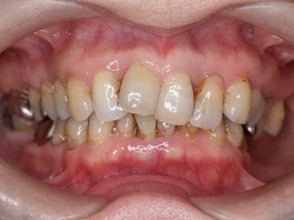

| 主訴 | 50代女性 以前いれた入れ歯が合わなくて使っていないので、しっかり噛めるようになりたい |

| 治療内容 | 矯正治療、インプラント治療、セラミック治療、金属床(部分入れ歯)を行いました。 |

| 治療費 | 4,200,000円(税込み) |

| 治療期間 | 2年(矯正治療期間 1年) |

| 治療回数 | 50回 |

| 想定されたリスク | 重度の歯周病で臼歯部の歯槽骨がかなり吸収していたため、インプラントが脱落するリスクがありました。 |